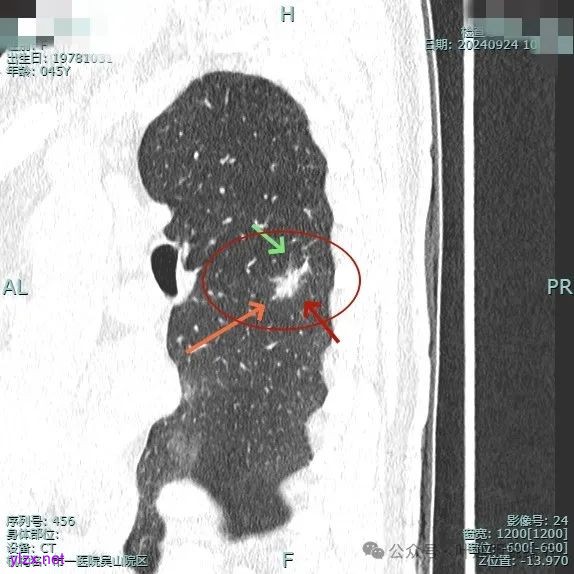

病灶3:

左下叶基底段微小结节,也是混合密度偏实性,瘤肺边界稍不清,与右侧的是类似形态的。

病灶混合密度,但瘤肺边界不够清楚,灶内也不太致密。

整个显得有点模糊,虽有血管进入,但血管说不上显著异常增粗,病灶边缘有细毛刺,贴胸膜近,但缺乏明显收缩力。

病灶显糊,轮廓较清但瘤肺边界欠清晰。

有血管进入,但病灶的感觉总好像缺乏收缩力,也聚拢性不太够。